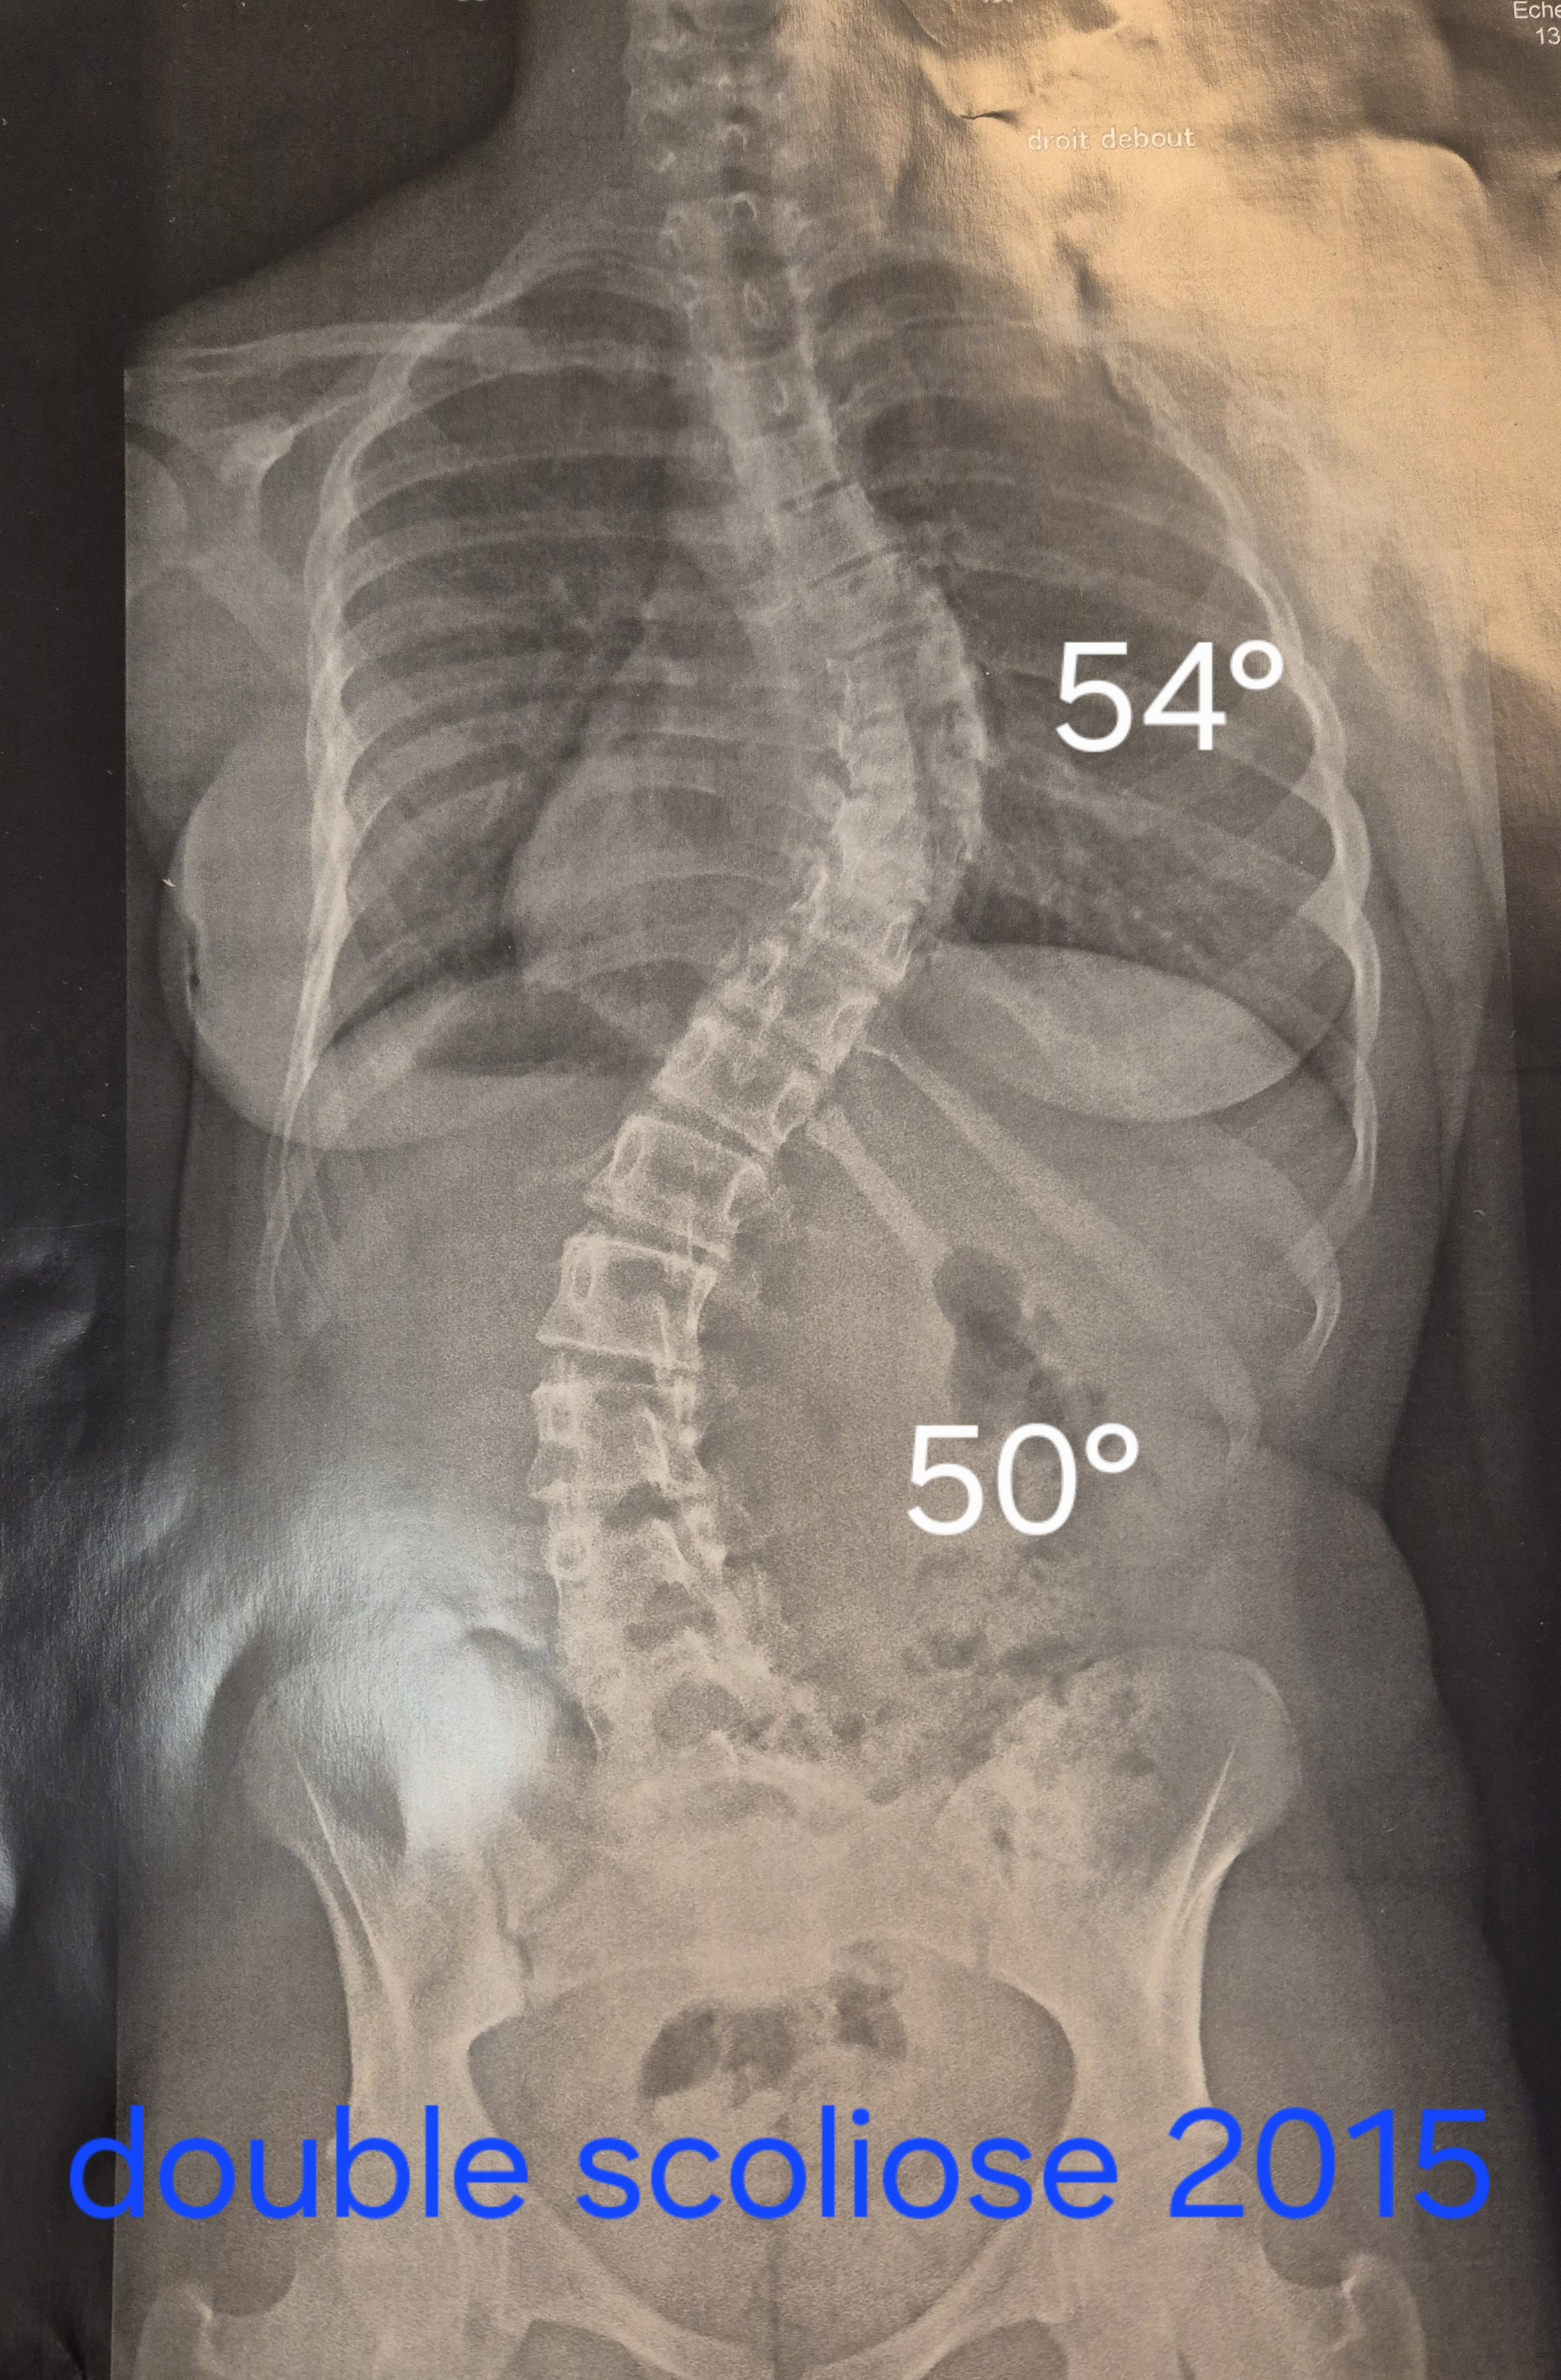

Les scolioses